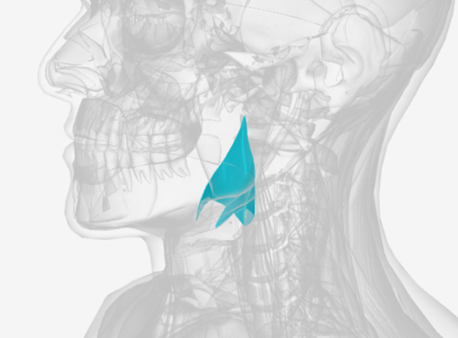

Superior pharyngeal constrictor

origin is on the pterygomandibular raphe, coursing posteriorly to insert on the median raphe of the pharyngeal aponeurosis function is to pull the pharyngeal wall forward to constrict the pharyngeal diameter